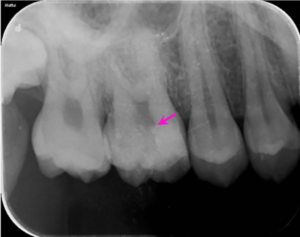

治療後1年

歯髄保存療法1年後のレントゲン写真です。矢印の部分に2次象牙質(歯の神経機能が正常なため神経に穴が開いた部分に自己再生能が働き象牙質が形成され閉鎖していました)が見られました。

電気的な検査で神経は正常でした。

自覚症状は全くありませんでした。